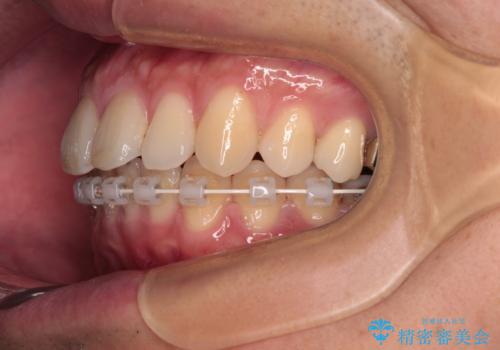

- 矯正装置

- ハーフリンガル

インビザラインは自己管理が煩わしく、表側のワイヤー装置は目立つので避けたいとのことで、上顎だけが裏側装置のハーフリンガルにて矯正治療を行うこととしました。

矯正治療中に結婚式があったそうですが、隙間も改善しており、一部装置を外すことなく挙式できたとのことでした。